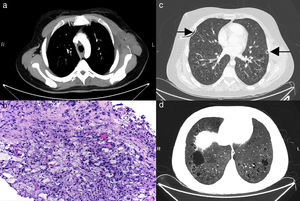

An acutely ill 22-year-old man was admitted to hospital with severe chest pain, high-grade dyspnoea and sinus tachycardia. He had a history of low-growth and polyostotic bone alterations since the age of 14. The patient presented 3 months before the current episode with a large left chest wall mass (Fig. 1) that was biopsied, showing xanthomatous CD68-positive, CD1a/S100 negative foamy histiocytes and BRAFV600E mutation, which confirmed Erdheim-Chester disease (ECD) (Fig. 1), as well as bone biopsy results. Emergency chest X-ray showed massive bilateral pneumothoraces, so chest tubes were placed (Fig. 1). Computed tomography (CT) demonstrated multiple lung cysts and diffuse interstitial thickening. Lung biopsy was positive. ECD is a rare non-Langerhans histiocytosis, with around 600 published cases to date,1 which primarily affects male patients between their 5th and 7th decades. More than 50% of ECD patients have BRAFV600E mutations.2 It encompasses a spectrum of manifestations: osseous, cardiovascular, pulmonary, central nervous system, orbital, neuroendocrine, retroperitoneal and cutaneous. Interstitial pulmonary disease and lung cysts appear in less than 18% of reported cases.3 To the best of our knowledge, there have been no cases of bilateral pneumothoraces and fewer than five cases of unilateral pneumothorax complicating ECD have been reported.

(a) Axial CT image demonstrating a large soft tissue mass in the left chest wall (asterisk). (b) Chest wall mass histological section confirming xanthomatous CD68-positive, CD1a/S100-negative foamy histiocytes with positive BRAF-V600E. (c) Axial CT image showing thorax drainage tubes due to bilateral pneumothoraces (arrows). (d) Note the striking interstitial involvement of both lungs with multiple lung cysts and diffuse thickening of the pulmonary interstitium.